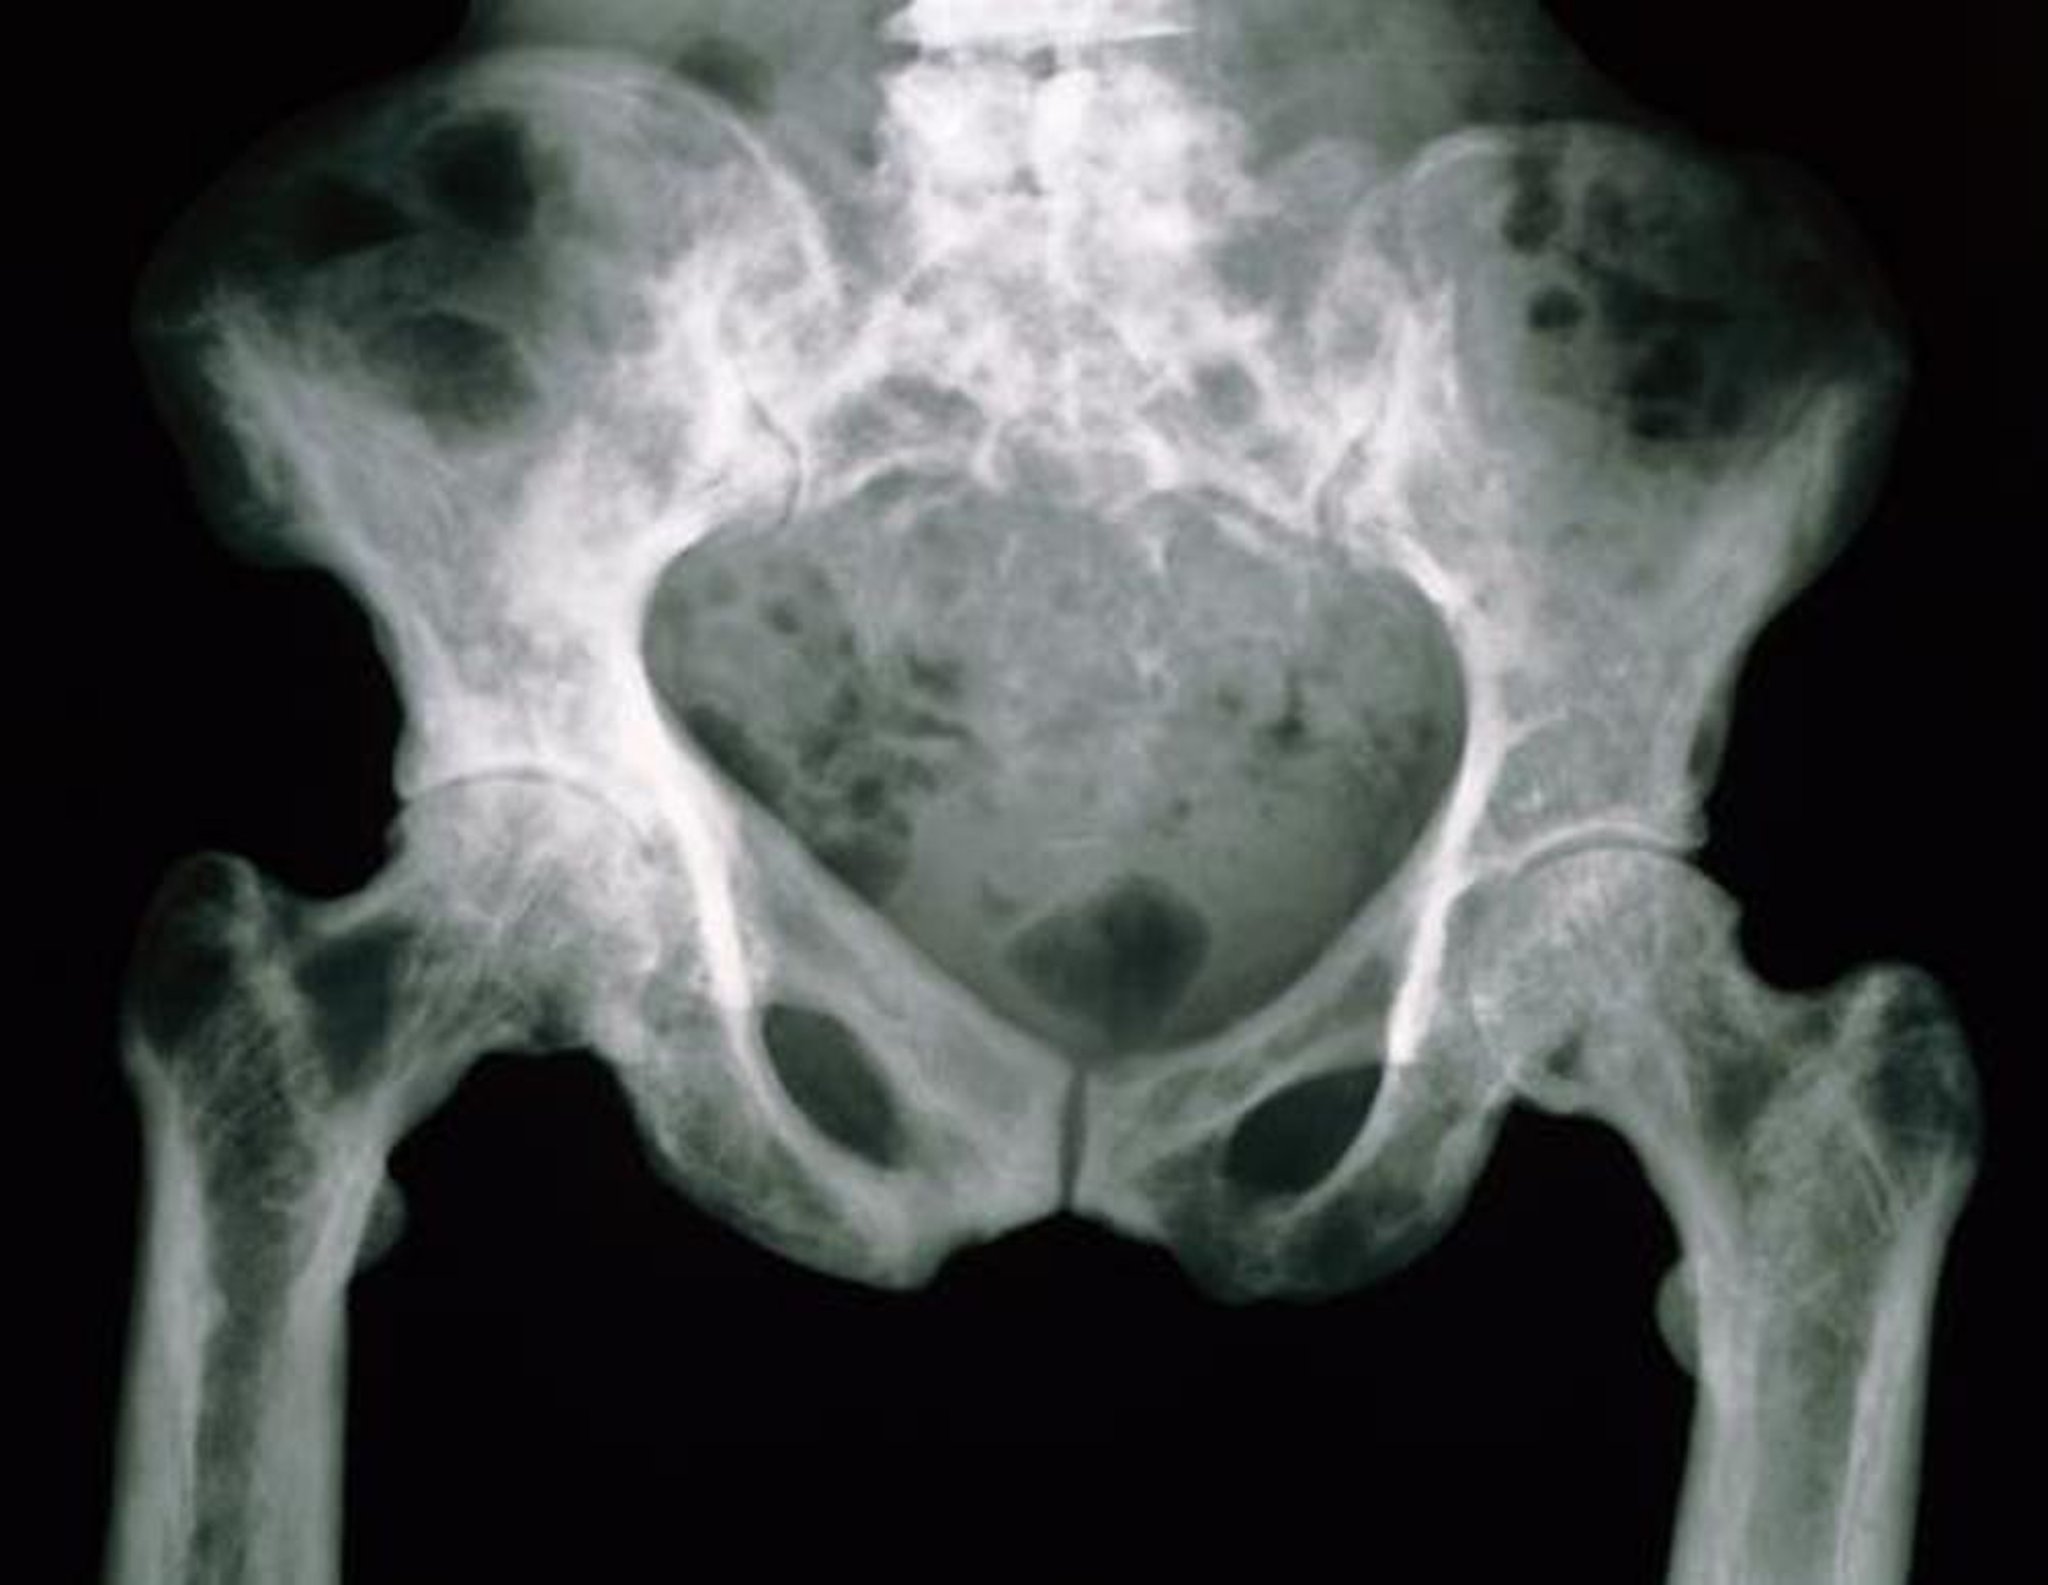

RX del bacino nella malattia di Paget

Le ossa pelviche in questa radiografia hanno un aspetto maculato a causa della loro maggiore porosità.